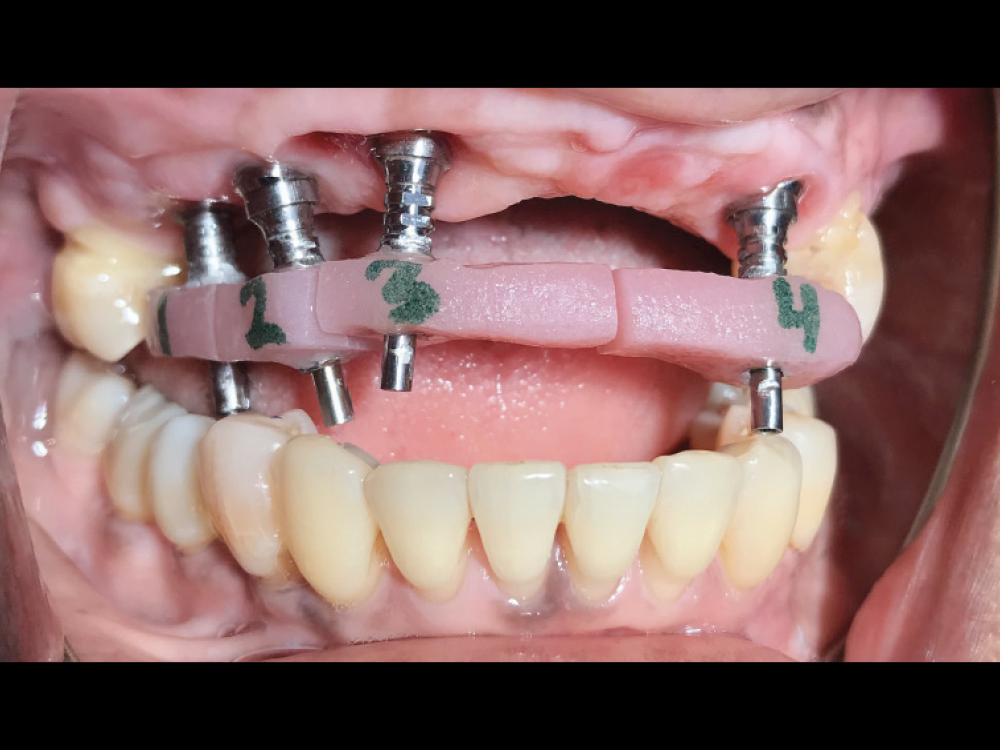

Multi-unit abutments connected to the implants

Figures 6a, 6b: Restoration fabrication went smoothly and efficiently thanks to the new and improved clinical workflow recently implemented at Glidewell, which includes step-by-step instructions, checklists and “how to” videos that simplify each appointment. Multi-unit abutments provided by the lab were connected to the implants and eased the seating of try-ins by elevating the restorative platform above the tissue level. The angled 17-degree multi-unit abutments ensured that the screw access holes would be located in the palatal areas of the restoration.

implant verification jig connected to implants and splinted together

Figure 7: An implant verification jig (IVJ) was connected to the implants and splinted together using cold-cure acrylic. The lab provides an IVJ for the final impression to make sure that the partial-arch restoration seats passively without putting strain on the implants.